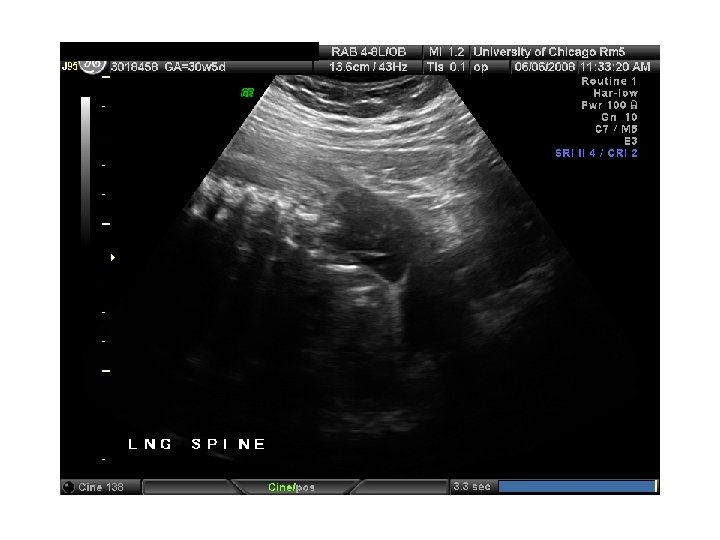

QUIZ What is Your Diagnosis? Case: Patient J. F. 30 years old, at 32 week gestation. Presented with the following pictures.

Answer: a) Trisomy 21 b) Non-immune Hydops c) Paravo virus Infection